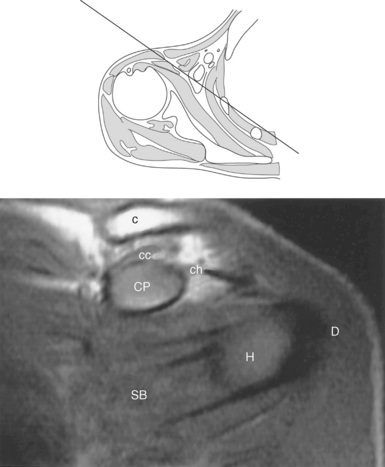

Figure 9.27 Axial, T1-weighted MR scan of shoulder.

Key: c, Clavicle; cc, coracoclavicular ligament; CP, coracoid process; ch, coracohumeral ligament; D, deltoid muscle; H, humeral head; SB, subscapularis muscle; SS, supraspinatus muscle; G, glenoid fossa; L, labrum; ss, supraspinatus tendon; b, tendon of long head of biceps muscle; IG, inferior glenohumeral ligament; mg, middle glenohumeral ligament; sb, subscapularis tendon; T, teres minor muscle.